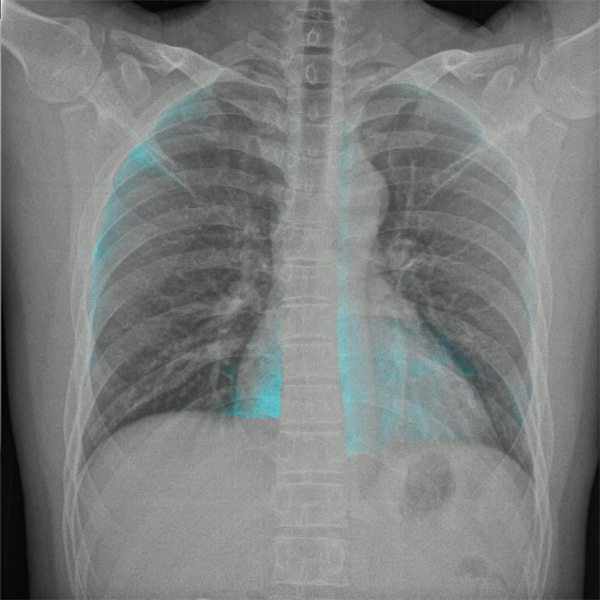

肺功能成像技术中的——肺通气可视化分析功能。基于动态DR实现的肺通气可视化可以在不打造影剂的情况下实现,它是通过患者肺部气流运动导致的肺部密度变化来进行成像,这就可以对潮气量进行相对评估,来检测肺叶单元的通气缺陷区域,并且可以对气体陷闭和气流受限进行鉴别诊断。那么通过肺通气可视化影像就可以更加直观地展现出患者呼吸过程中通气量减少的异常区域,并且对空气潴留及通气限制进行评估,为COPD早筛提供一种简单、低成本、低侵袭的日常化影像学检查方法。

(肺通气可视化图像)